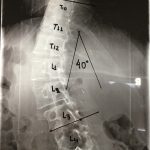

(γ) Ορθία στάση, ουδέτερη θέση. Παρατηρείται αριστερά θωρακο-οσφυϊκή σκολίωση (Θ10-Ο3) 55 μοίρες κατά Cobb

(β,δ) Υπτία θέση υπό έλξη. Παρατηρείται μείωση της σκολίωσης στις 40 μοίρες γεγονός που δείχνει τη μεγάλη δυσκαμψία της σκολιωτικής παραμόρφωσης